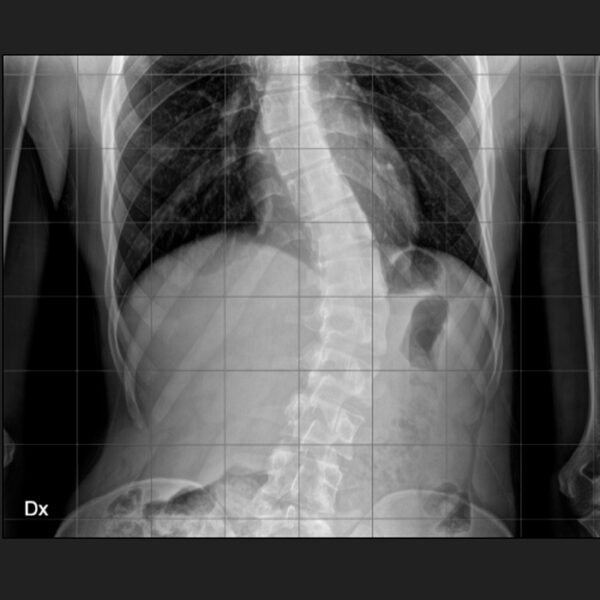

Intervento chirurgico eseguito:

Artrodesi dorso lombare con osteotomie correttive

Radiografia della colonna in toto post-operatoria